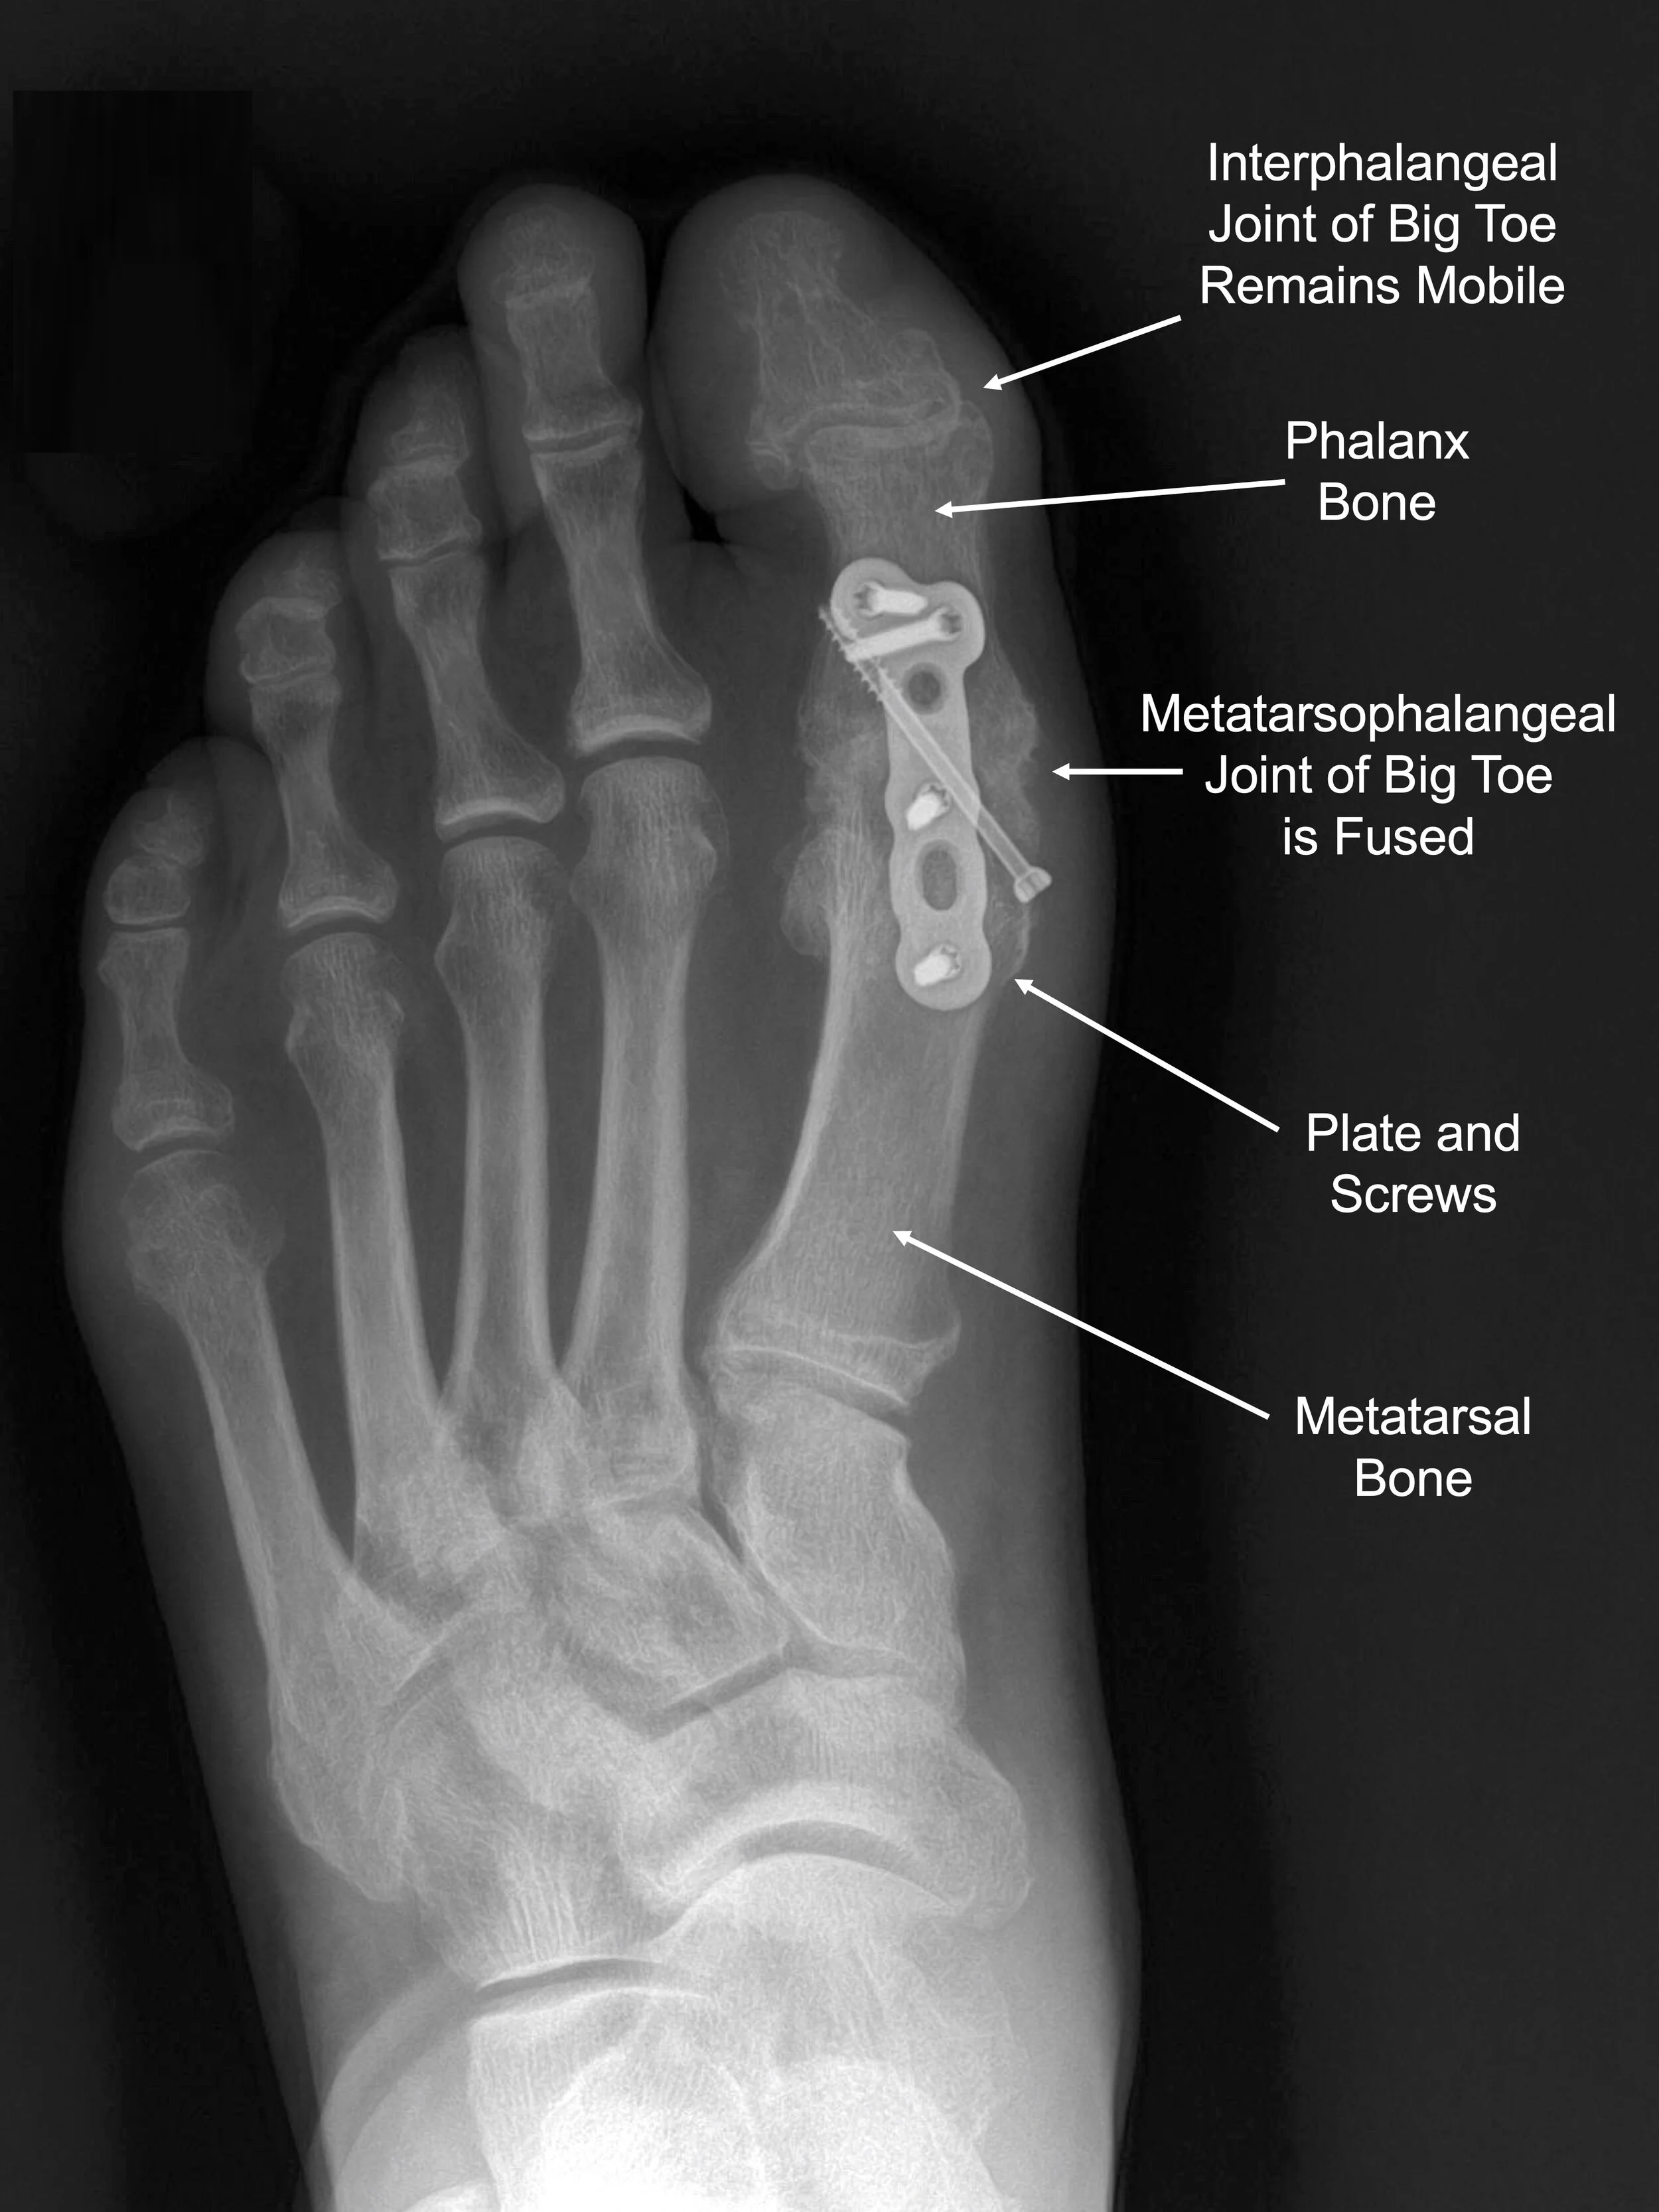

Big Toe Arthritis — Daniel Bohl, MD Midwest Orthopaedics at RUSH

From www.danielbohl.com

Big Toe Arthritis — Daniel Bohl, MD Midwest Orthopaedics at RUSH Arthritis In Toes Joint Learn how osteoarthritis (oa) affects the big toe joint, also known as the hallux, and what are the options for pain relief and. Arthritis in toes can cause pain, stiffness, swelling, and difficulty walking. Treatment may include pain relievers, ice. (also known as big toe joint osteoarthritis) a common condition that affects the big toe joint known as 1st metatarsal. Arthritis In Toes Joint.